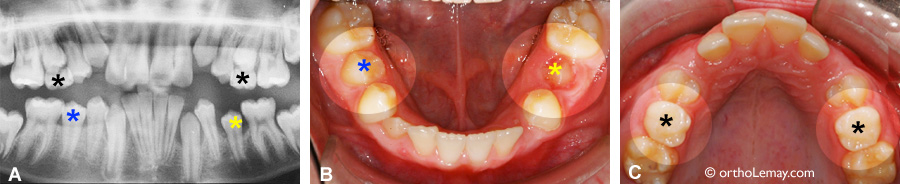

À l’opposé, comme l’illustre l’exemple suivant, l’espace de dérive inférieur droit a été perdu lorsque la deuxième molaire temporaire a été extraite et qu’aucun mainteneur d’espace n’a été utilisé pour empêcher la migration des dents. La prémolaire (*) se trouve bloquée par les dents qui ont basculé de part et d’autre de l’espace d’extraction.

(A) Radiographie montrant la prémolaire (*) bloquée suite à la migration des dents adjacentes (flèches). (B) À l’arcade supérieure, les dents supérieurs ont migré vers l’avant et “volé” de l’espace aux canines qui sont bloquées à l’extérieur de l’arcade (flèches). (C et D) Vue des dents basculées bloquant la prémolaire (*) correspondant à la radiographie (A).